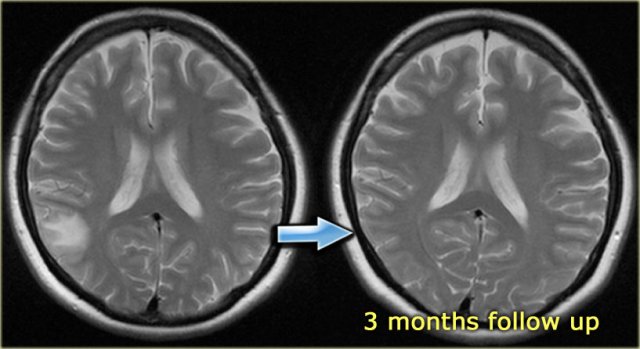

On the left DSA images of a patient with a DAVF.

Notice the direct communication between the branches of the external carotid artery and the transverse sinus (blue arrow).

Continue with the T2-weighted images.

On the left T2-images during the follow up.

In april 2008 there were no abnormalities.

In january 2009 there are signs of intracranial hypertension like CSF surrounding the optic nerve and CSF within the stalk of the hypophysis.